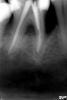

Стоматологша Опубликовано 3 февраля, 2011 Автор Поделиться Опубликовано 3 февраля, 2011 (изменено) вы знаете, мне вам здесь и возразить то особо нечего, я собственно об этом же речь и вела) халтура она и есть халтура, хоть вкладка, хоть штифт. дополнительно я пыталась сказать о том, что если доктор успешно фиксирует штифты, пусть фиксирует, если успешно получаются вкладки, то пожалуйста, пусть это будут вкладки.но нужно понимать, что вкладка накладывает на доктора повышенные обязательства относительно эндодонтии. об этом порой забывают, вот пример из последнего, выкладывала в хирургииhttp://s007.radikal.ru/i300/1012/83/9f2c347e2db9.jpgпациент обратился с выраженным отеком, вскрыли, то се... отправила в члх, потом он приходил с кт - кости вестибулярно как и предполагалось нет, дырка в пазуху, которая практически полностью заполнена огромной кистой, пациент шутник, затребовал чтобы я ему сделала пломбировку ретроградно вот этого, а потом его в члх прооперируют не взялась, ушел дальше искать свое счастье... еще одна проблема тех, кто тяготеет к вкладкам это восстанавливать ими сильно разрушенные зубы с практически отсутствующим ферулом. служит такая конструкция год-два, потом расцементировка - подвижность - трещина корня. удалением такой прелести я закончила прошедший год, выковыривала почти час. снимка к сожалению дома нет. а вот интересное опг по вашей просьбе, пришло недавноhttp://i011.radikal.ru/1102/0a/c8eae87059a2.jpg42, 43, 44 имеют вложения из ортодонтической проволоки, так... чиста касметичски; 33, 34 штифты, мостовидный протез тоже поражает воображение, практически взлетно-посадочная полоса) понятно, что канал нужно разрабатывать правильно при всех методиках, но так же важное условие - это тот самый пресловутый ферул, и чем больше, тем лучше. при наличии хорошего оного будет стоять и функционировать и штифт и вкладка, потому как большая нагрузка приходится на шейку зуба, а она своя - родная. а вечного нет ничего. штифт позволяет с течением времени исправить ошибки и изготовить ту же самую вкладку, а вот вкладка далеко не всегда. вы посмотритрите на витающие на протяжении последних лет тенденции в эндодонтических кругах обтурировать все в одно посещение. лично я неоднократно после себя же, во второе посещение находила дополнительные ответвления внутри уже обработанных каналов, которые были бы упущены. но даже при контроле самой себя же ни я, ни кто-либо другой не может дать 100% гарантий на эндо, успех определяется временем. каково количество проводимых докторами ретритов? оно огромно! а вот теперь представьте, что все эти зубы были бы восстановлены вкладками. большая часть таких зубов была бы попросту удалена.нет уж, нет уж, лучче штифты.ЗЫ: сама работаю свш, причем даже не уверена на все 100 что это самый лучший метод, но предпочитаю заканчивать зубы самостоятельно. Согласна на 100 % и поэтому тоже предпочитаю заканчивать самостоятельно, даже если ортопед настаивает на эндо и вкладке зуба, который по мне нужно удалять. Зуб "лечен" РФ методом при царе Горохе, но пац не хочет его удалять. согласен ещё чуть-чуть с ним пожить. Конечно никакого ферула нет ни медиально, ни дистально, но желание пациента - закон. На снимке процесс примерки ВКВ разборной. Изменено 3 февраля, 2011 пользователем Стоматологша Ссылка на комментарий